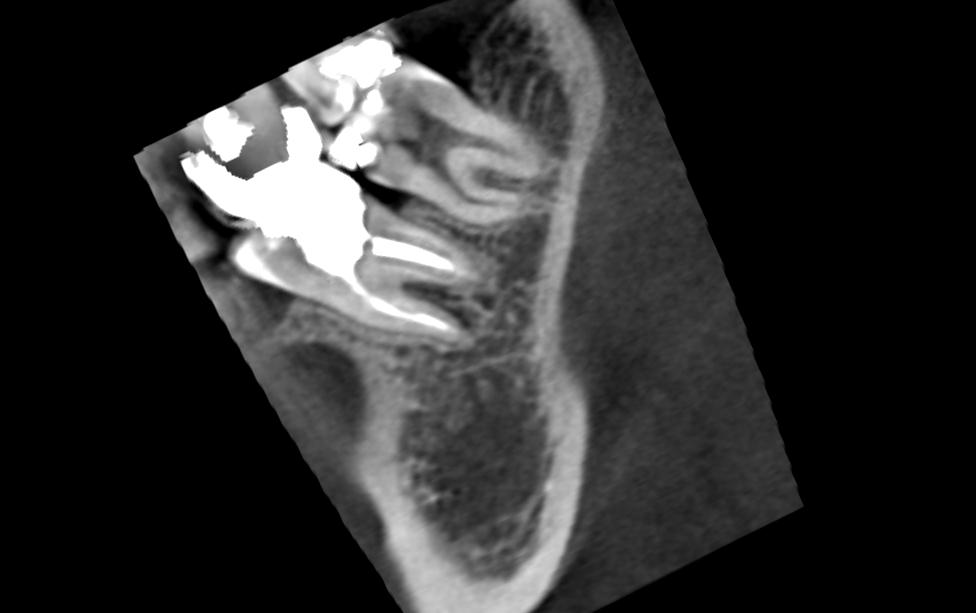

А вот такие снимки чтото скажут:Нажмите на изображение для увеличения

Название: Image5.jpg

Просмотров: 62

Размер:	32.0 Кб

ID:	4314306Нажмите на изображение для увеличения

Ну в чем же вода - все сходятся на том, что надо удалять. Не затягивая, т.к свищ по проекции межкорневой гранулемы и грануляции сособсвуют разрушению кости, чем дальше, тем больше... И потом тяжело будет имплант ставить... Куда уж конкретнее?!?

Проблема в том, что даже идеальная перепломбировка каналов гранулему не уберет, а при попытке оперативно убрать гранулему, убрать всю пломбу чтобы получить доступ к каналам и перелечить каналы, пройдя по изогнутым каналам мимо заломанного инструмента, от зуба ничего не останется.... "выкрасить и выбросить"...